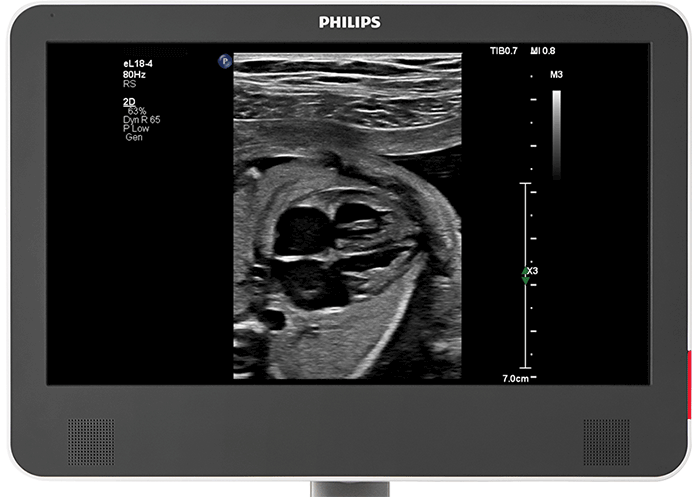

Superb imaging details for The Philips eL18-4 PureWave transducer provides superb 2D detail resolution, along with the penetration needed for diagnostic confidence in first and

2D TTE for your tiniest patients The revolutionary size of the Philips multiplane